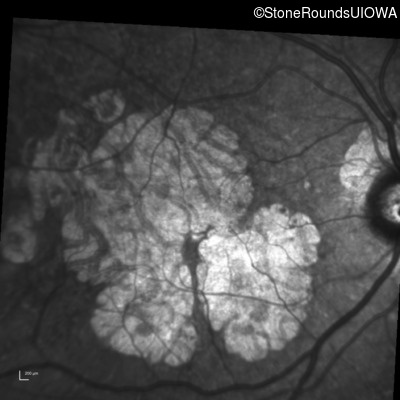

Infrared Fundus Photograph - Right - 20/25

Exemplar

Infrared Fundus Photograph - Left - 20/32 -2